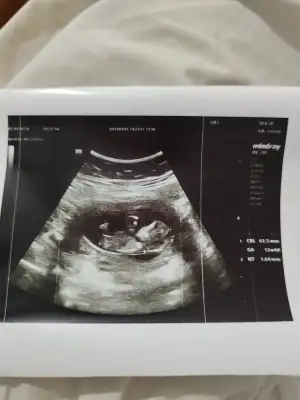

kızlar çıktım kontrolden. 12+2 tam günü gününe. Asker selamı verdi sürekli çok komikti:) nub a göre erkeğe yakın ama çok da dik değil bazen klitoris de böyle görünüyor kan testini bekleyeceğiz. Valla bi fikriniz varsa siz de bakın:)

Hem asker pozunu, hem nubun belli olduğunu atıyorum:)

Nubu yatay gibi😊 kıza daha yakın bence